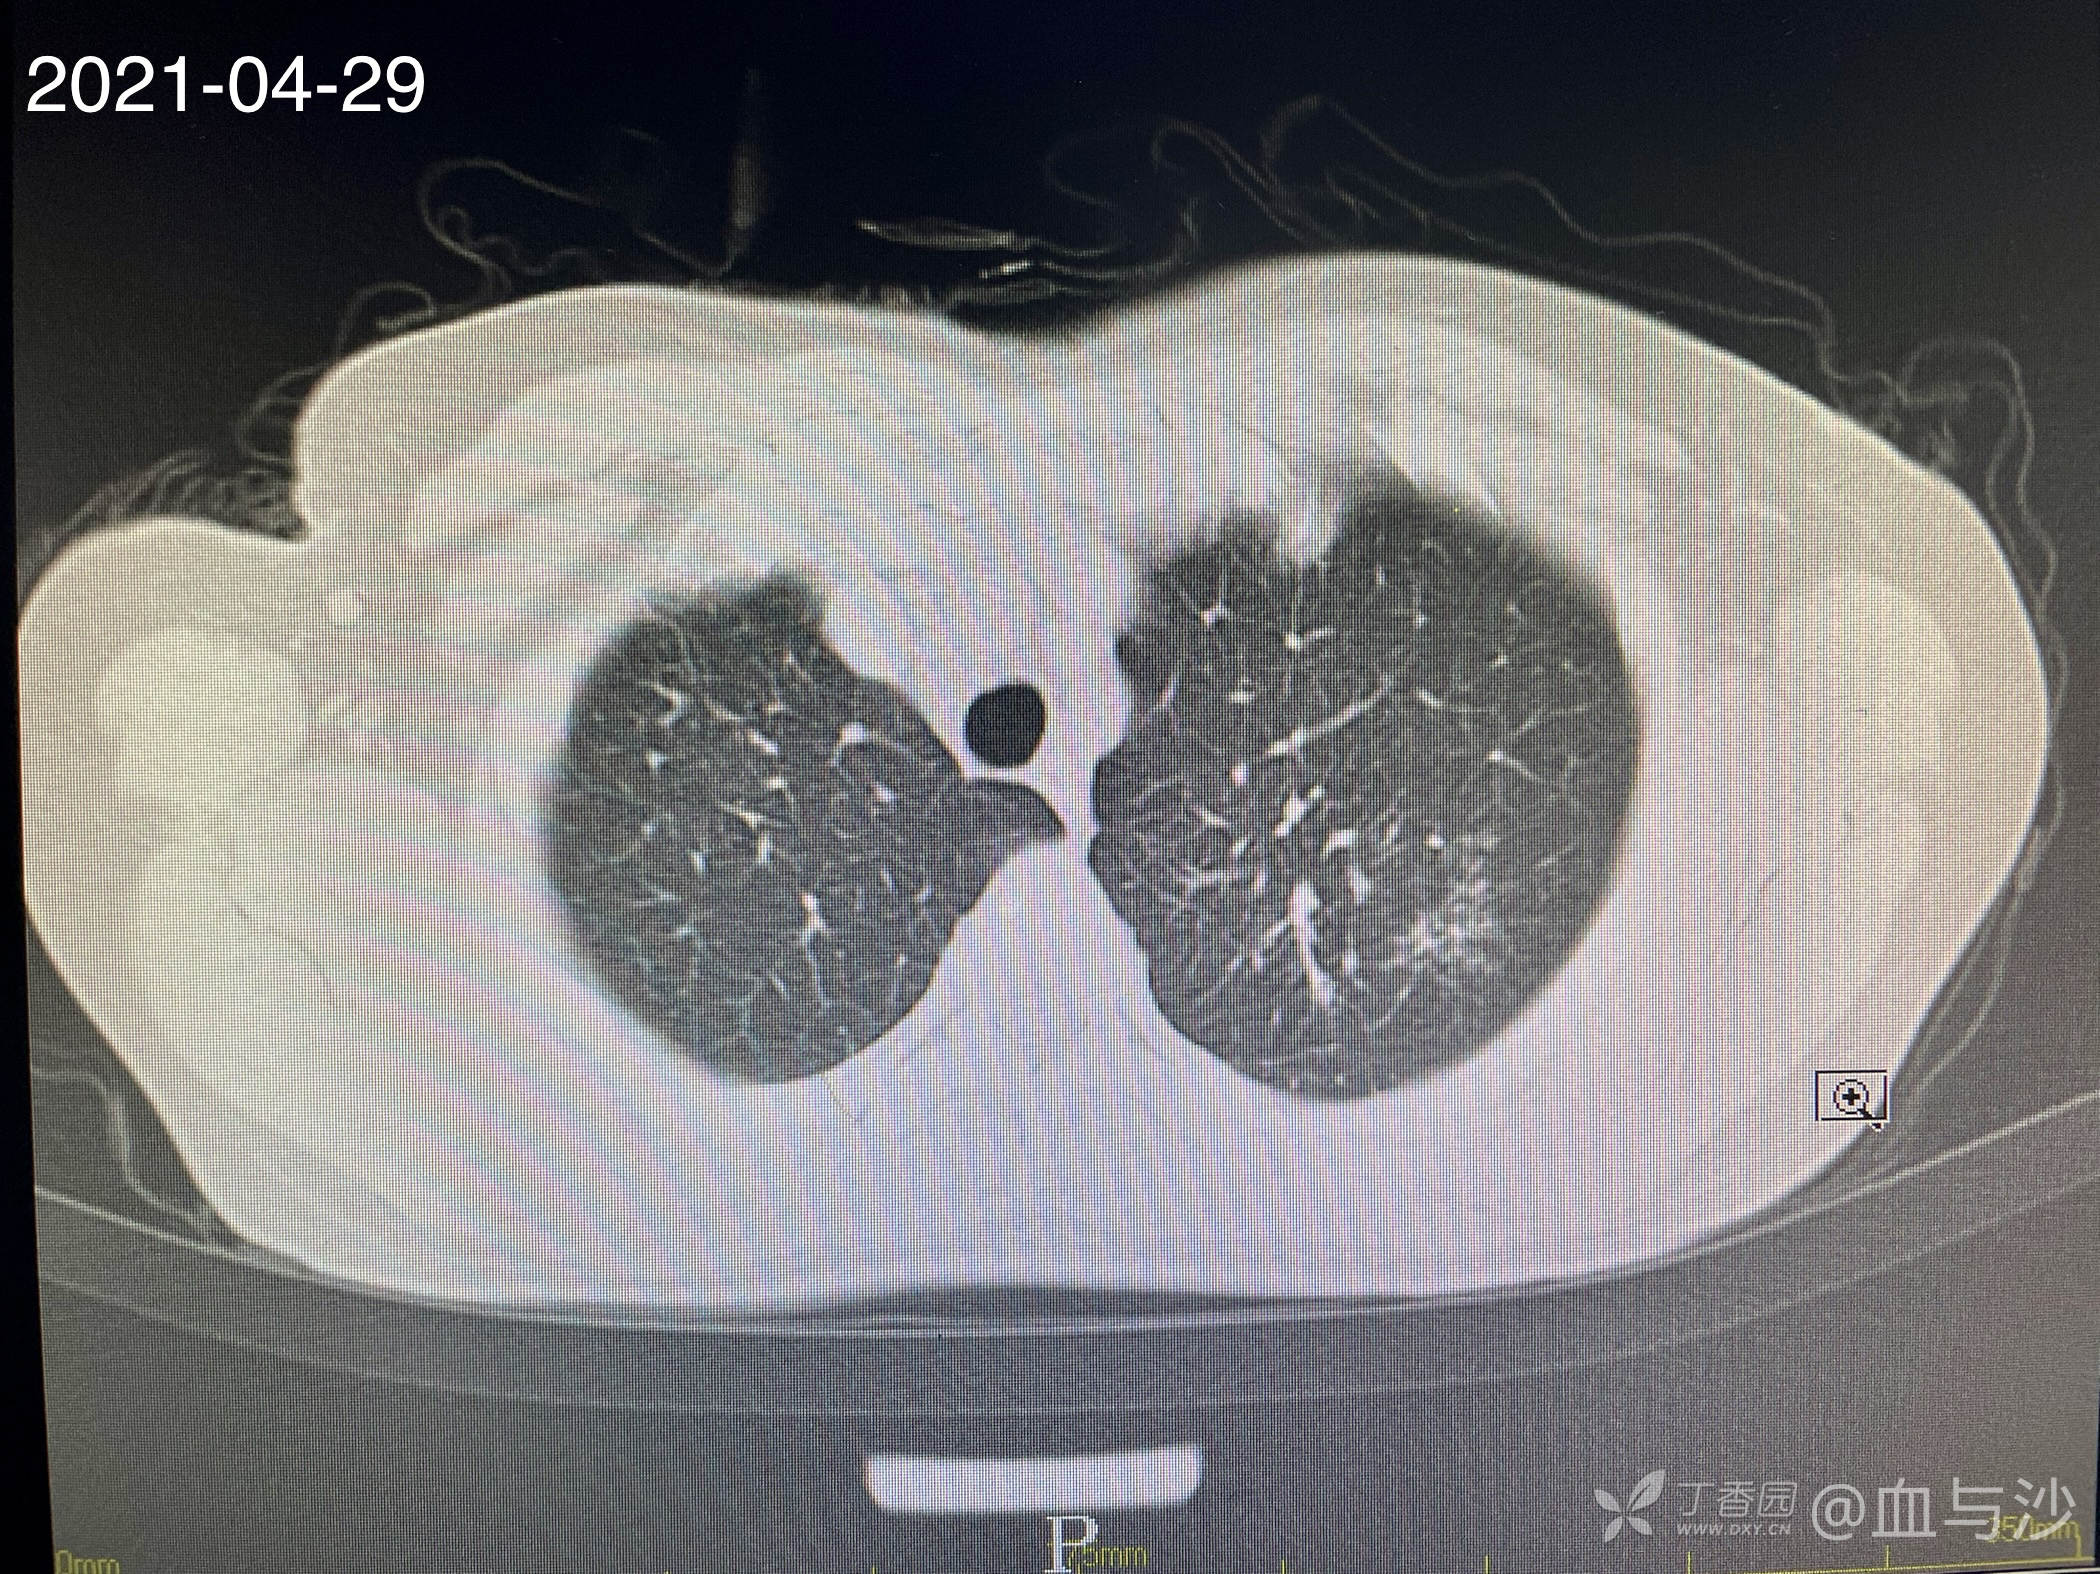

病人女,60岁,去年4月底因咳嗽发热入院,诊断支气管扩张伴感染(结核各项检查阴性,病人平时也无潮热盗汗),予抗感染对症处理。当时CT片左肺上叶有一磨玻璃样影。今年5月病人再次咳嗽发热入院,续按照支扩伴感染处理,但CT显示去年的磨玻璃影成了一约1.5cm的实性结节。